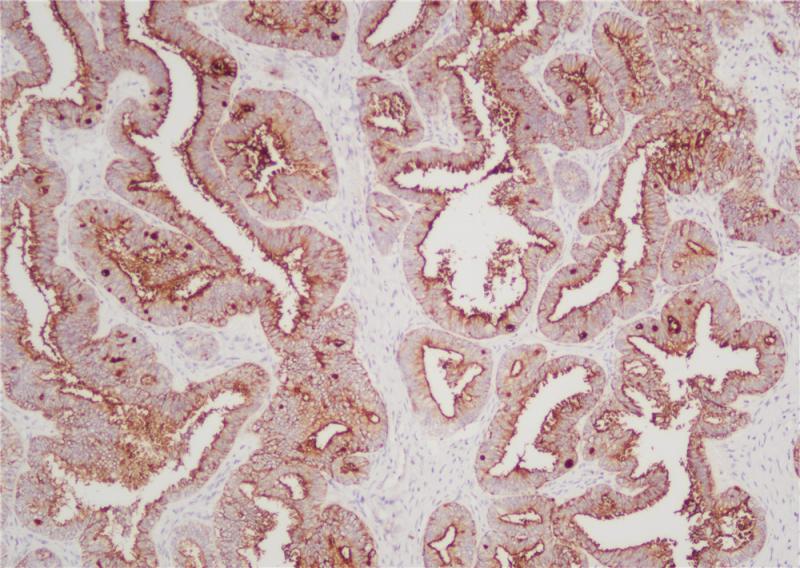

AMACR (P504S蛋白)在支链脂肪酸及其衍生物的β -氧化中起作用。AMACR存在于前列腺、肝、胆道、肾、肺等多种组织的线粒体和过氧化物酶体中。在90%以上的前列腺癌中发现了AMACR的弥漫染色模式。AMACR抗体主要用于前列腺癌的临床诊断。